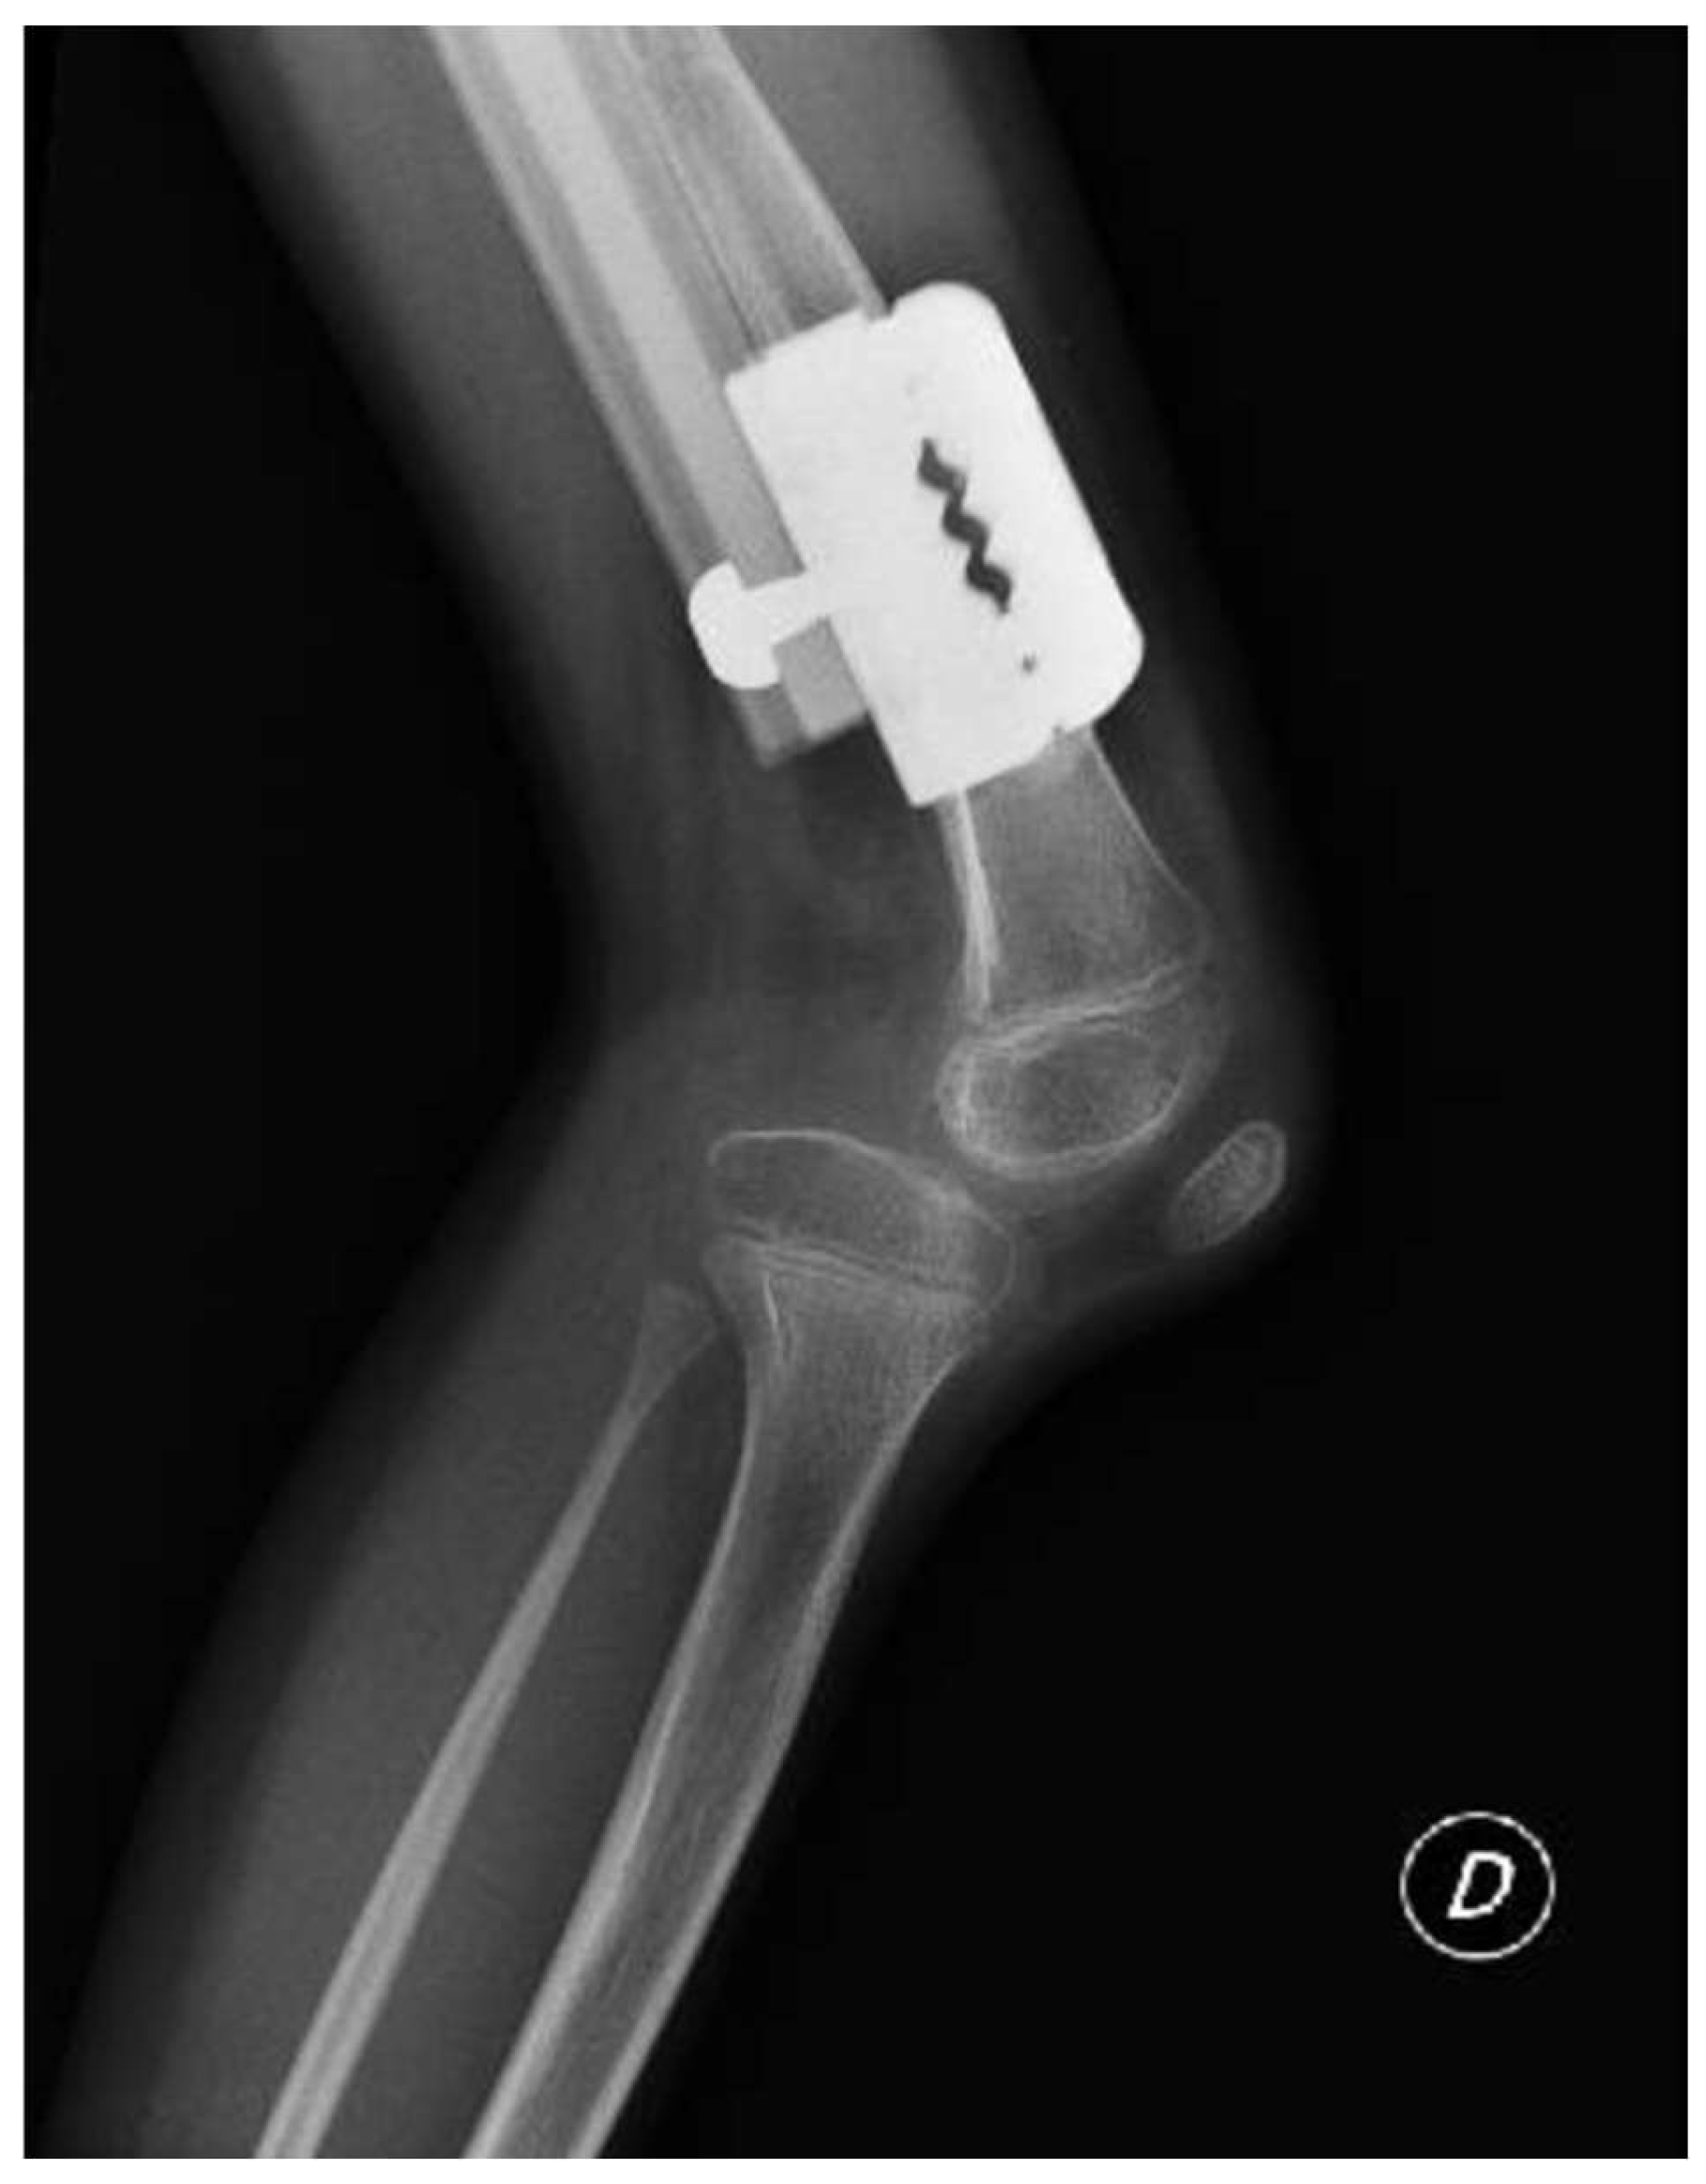

The patient was instructed to start physical therapy for hip and knee range of motion immediately after surgery, while progressive weight-bearing was commenced on the last day of lengthening. At 12 weeks the lengthening goal, 60 mm, was achieved. At 5-months follow up, lower-limb weight-bearing plain radiographs demonstrated that the right femur was within 5 mm of length of the left femur and bone regeneration was visible in the osteotomy gap, however, the study was limited by the inability to fully extend the right knee (Figure 2). Lateral projection radiographs of the right knee showed posterior subluxation of the tibia with respect to the femoral condyles (Figure 3). No action was taken at the time.

Figure 3. caption.